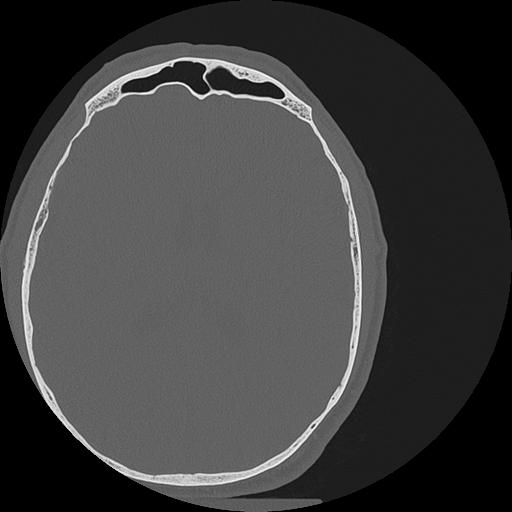

7 HUESO,,Vol,0.5,HUESO,,